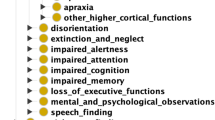

Radiology teaching file repositories contain a large amount of information about patient health and radiologist interpretation of medical findings. Although valuable for radiology education, the use of teaching file repositories has been hindered by the ability to perform advanced searches on these repositories given the unstructured format of the data and the sparseness of the different repositories. Our term coverage analysis of two major medical ontologies, Radiology Lexicon (RadLex) and Unified Medical Language System (UMLS) Systematized Nomenclature of Medicine Clinical Terms (SNOMED CT), and two teaching file repositories, Medical Imaging Resource Community (MIRC) and MyPacs, showed that both ontologies combined cover 56.3% of terms in the MIRC and only 17.9% of terms in MyPacs. Furthermore, the overlap between the two ontologies (i.e., terms included by both the RadLex and UMLS SNOMED CT) was a mere 5.6% for the MIRC and 2% for the RadLex. Clustering the content of the teaching file repositories showed that they focus on different diagnostic areas within radiology. The MIRC teaching file covers mostly pediatric cases; a few cases are female patients with heart-, chest-, and bone-related diseases. The MyPacs contains a range of different diseases with no focus on a particular disease category, gender, or age group. MyPacs also provides a wide variety of cases related to the neck, face, heart, chest, and breast. These findings provide valuable insights on what new cases should be added or how existent cases may be integrated to provide more comprehensive data repositories. Similarly, the low-term coverage by the ontologies shows the need to expand ontologies with new terminology such as new terms learned from these teaching file repositories and validated by experts. While our methodology to organize and index data using clustering approaches and medical ontologies is applied to teaching file repositories, it can be applied to any other medical clinical data.